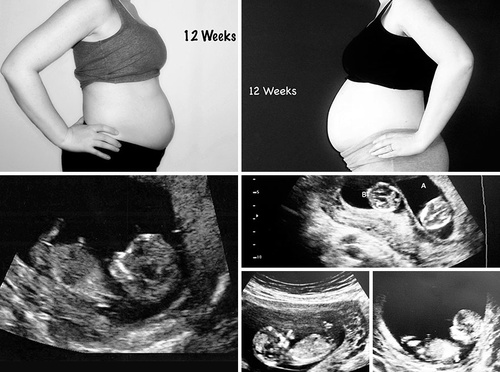

Cum arată o sarcină monofetală, comparativ cu una gemelară. Povestea emoţionantă a femeii care s-a luptat ani buni să poată deveni mamă